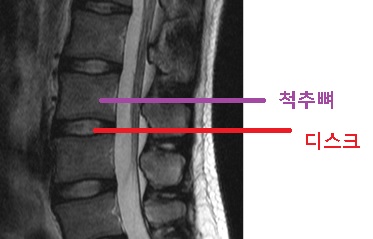

척추 디스크는 척추 각 부위에서 발생하는 디스크로, 척추 간판이라고도 불립니다.

척추 디스크는 척추뼈와 척추 사이의 완충재 역할을 합니다.

척추 디스크는 두 개의 주요 부분으로 구성됩니다.

외부 원형 인대 또는 편평한 원반과 내부 젤 상태의 물질로, 젤러스 핵이라고 불리는 부분입니다.

인대는 디스크의 외부 부분을 감싸며, 내부 젤 상태의 물질은 디스크의 중앙 부분을 채웁니다.

이 중앙 부분은 척추 충격을 흡수하고 척추 디스크가 완충제 역할을 수행하는 주된 이유입니다.